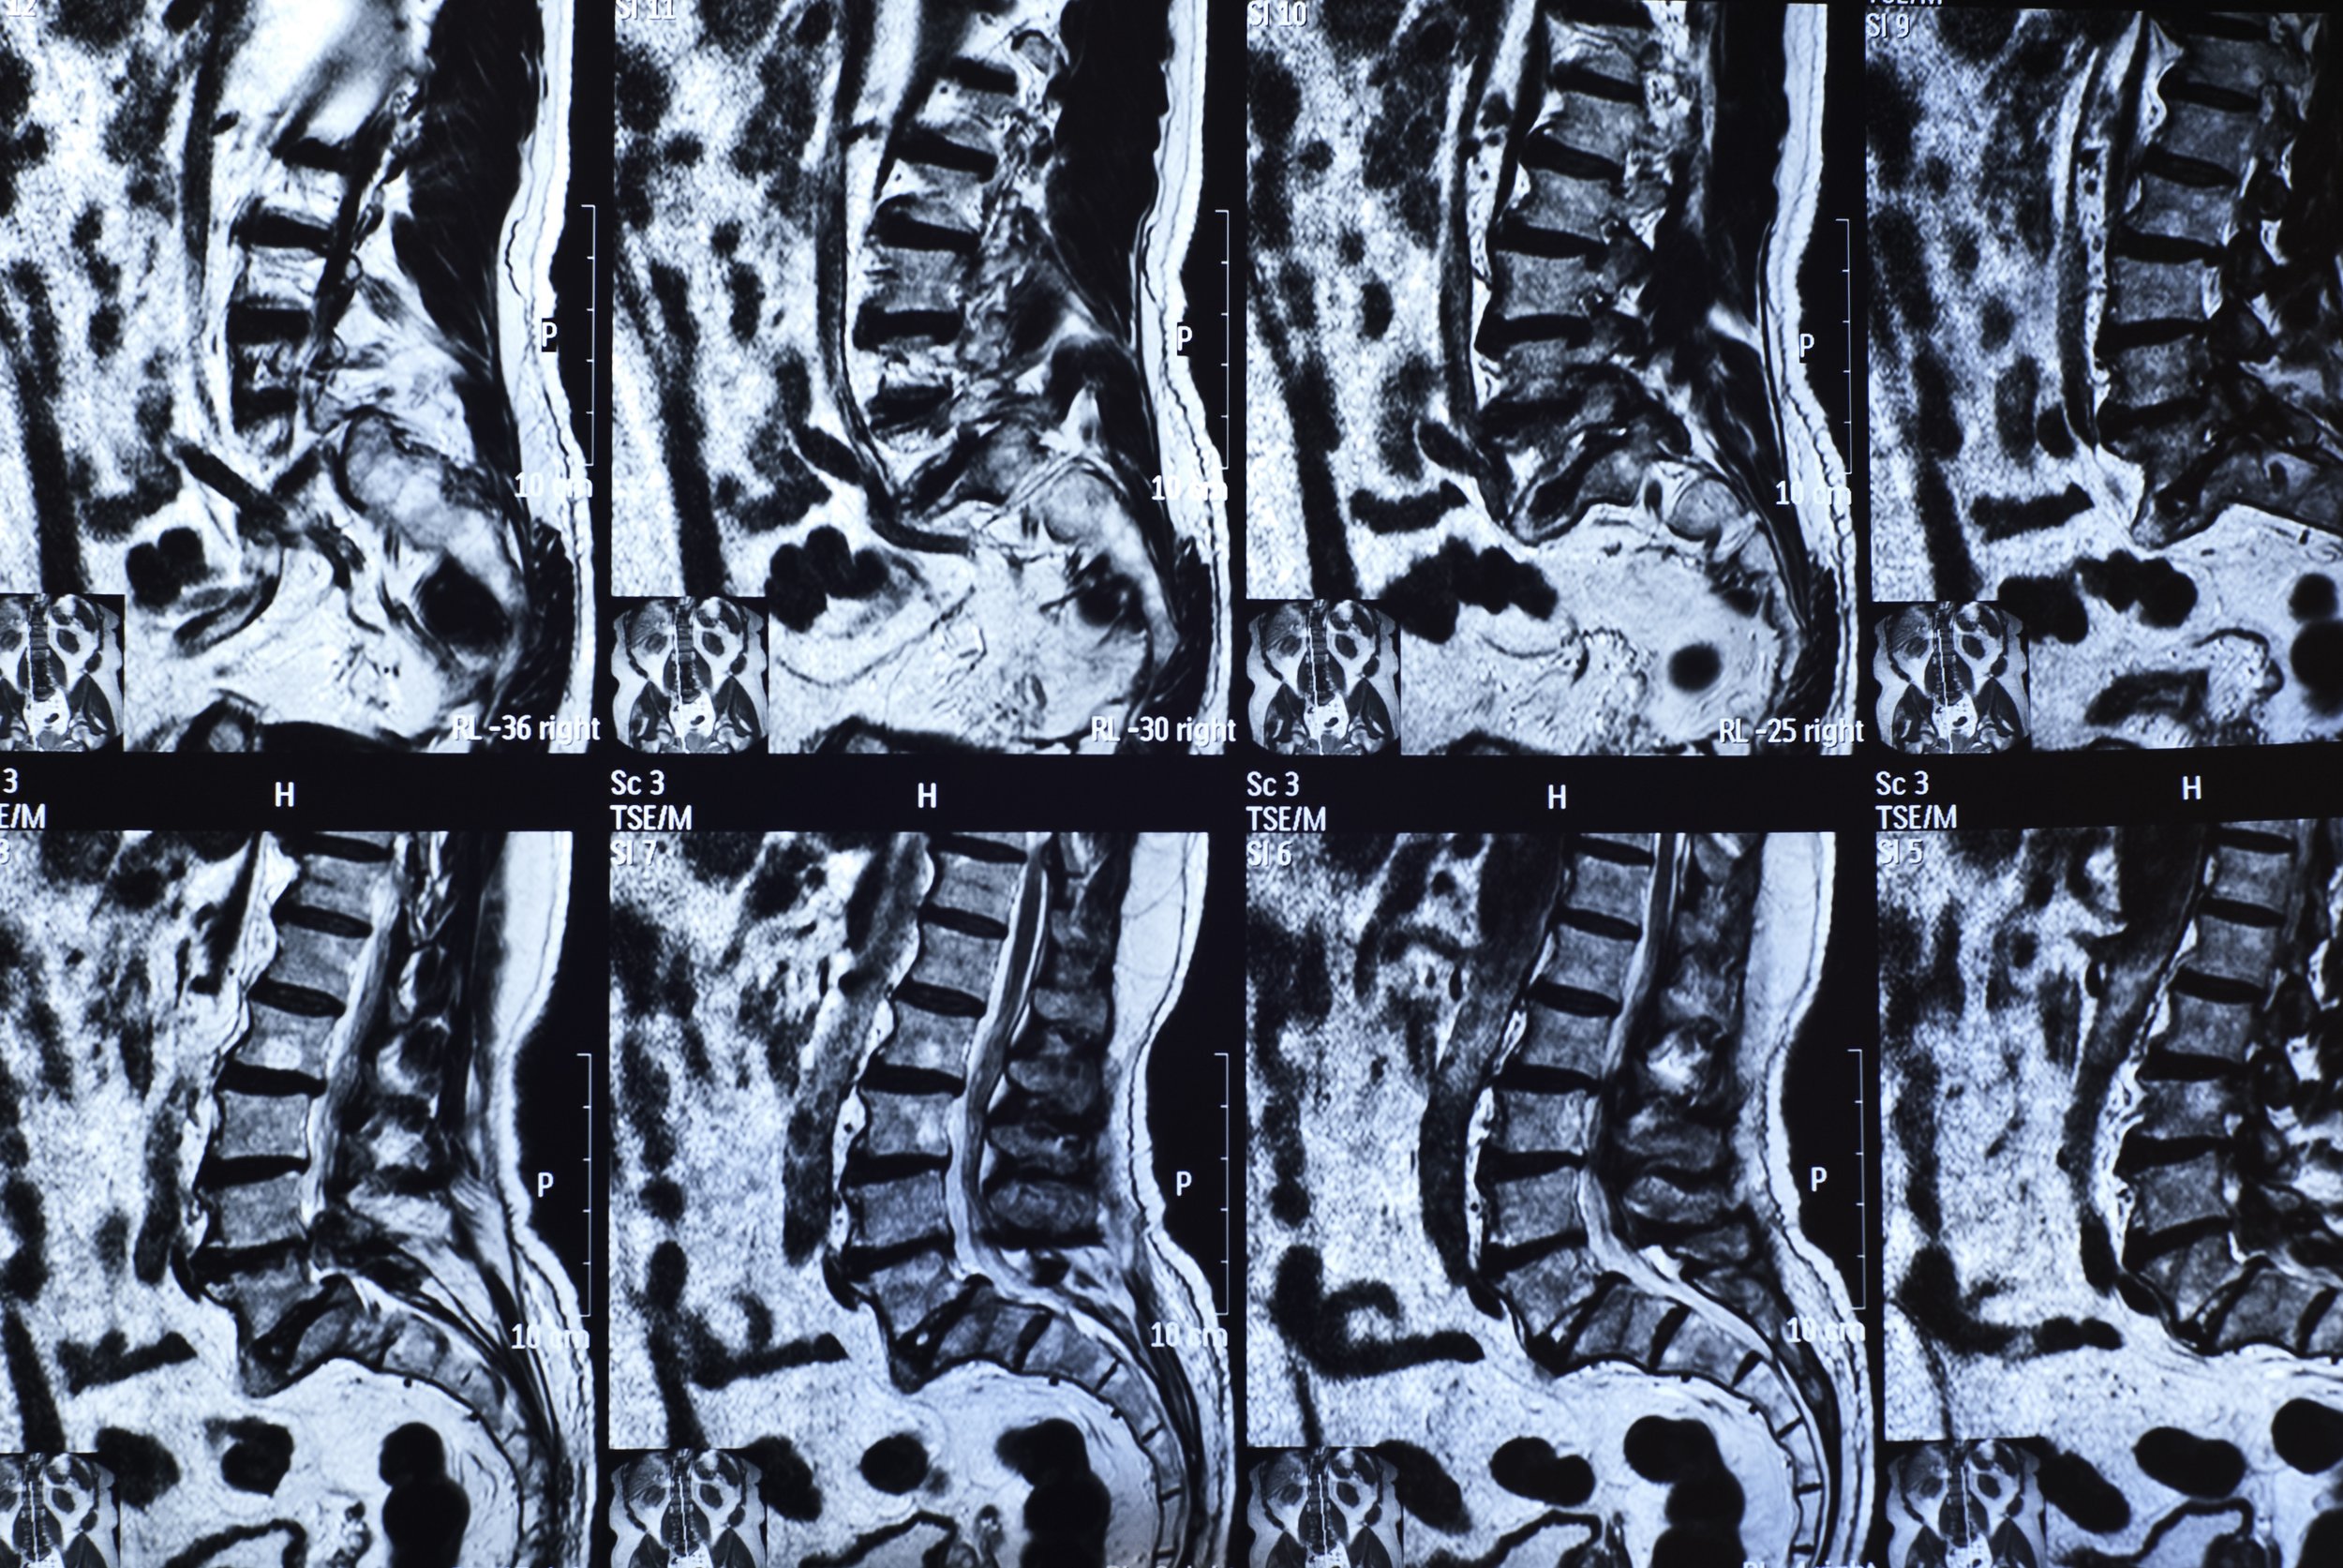

Disorder of the Spinal Column

Spine surgery includes treatment of the spinal column, or the support structures around the spinal cord and spinal nerves. Compression or constriction of the nerves and spinal cord by the bony overgrowth of the spine or herniated disks can cause pain, sensory changes or weakness. Treatment often requires decompression (removal of abnormal bone growth/herniated disks) of the spinal cord and nerves to alleviate symptoms. Spinal column disorders requiring surgery range from degenerative processes to traumatic injury to tumors. In some circumstances the stability of the spine is affected. When needed, spinal fusion with or without instrumentation or "hardware," is used to re-establish spinal stability. Minimally invasive techniques and microsurgical techniques are utilized when appropriate to get the best results for the patient.

Disorder of the Spinal Nerve

The problems involving the spinal nerves often come from compression. Degeneration and herniation of the disks in the neck, back and low back can compress spinal nerves as they exit the spinal column. Symptoms can range from numbness to pain to weakness in an arm or leg and difficulty walking. Surgery might include removal of all or part of the disk. If the whole disk is removed, spinal fusion is usually required to maintain stability of the spine. Degeneration of joints in the spine can also cause spinal nerve compression giving very similar symptoms. Finally, tumors of the nerves themselves can cause pain and dysfunction. All of these can be treated surgically if indicated.

Lumbar Fusion (Open and MIS)

In cases of instability of the spine associated with spondylolisthesis a lumbar fusion with decompression is needed. This can be done using an MIS technique using percutaneous pedicle screws or cortical bone screws in an open technique. Fusion is used in cases of instability or fracture. This operation decompresses the spine and fuses the segment (s) that are unstable.